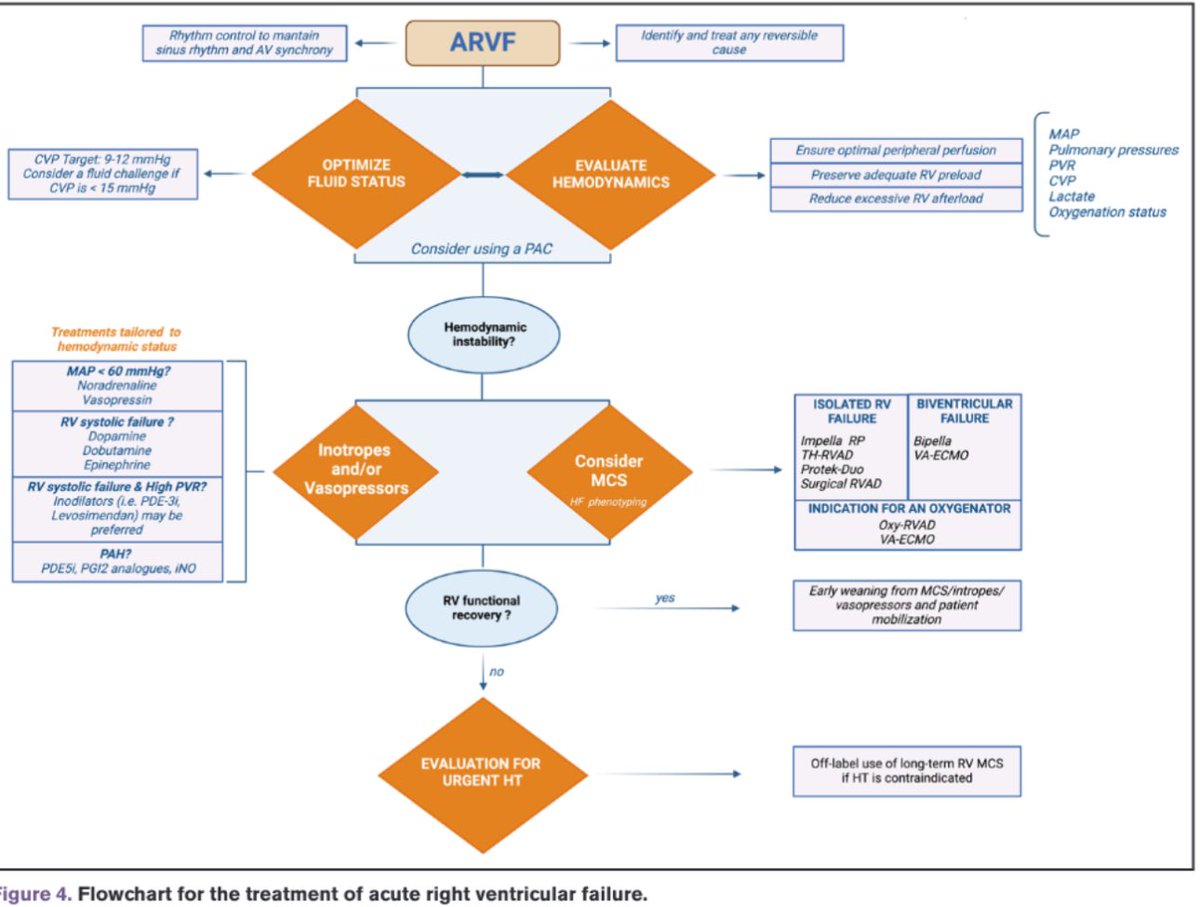

Gaps and Knowledge in the Contemporary Management of Acute Right Ventricular Failure ahajournals.org/doi/10.1161/CI… Circulation #RVFailure #HeartFailure #CardioEd Circ: Heart Failure